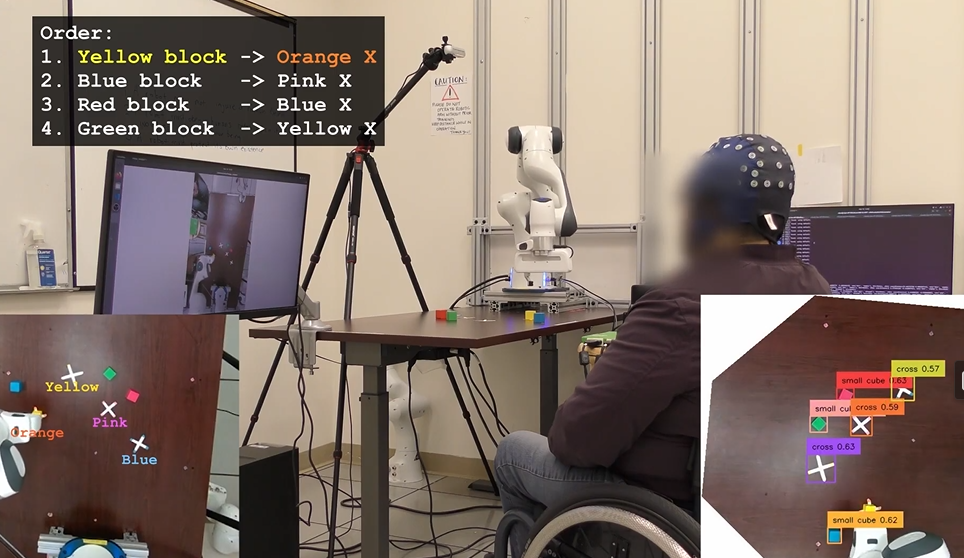

“AI副駕”大幅提升腦機(jī)接口操控力

2025-09-05 01:01:00